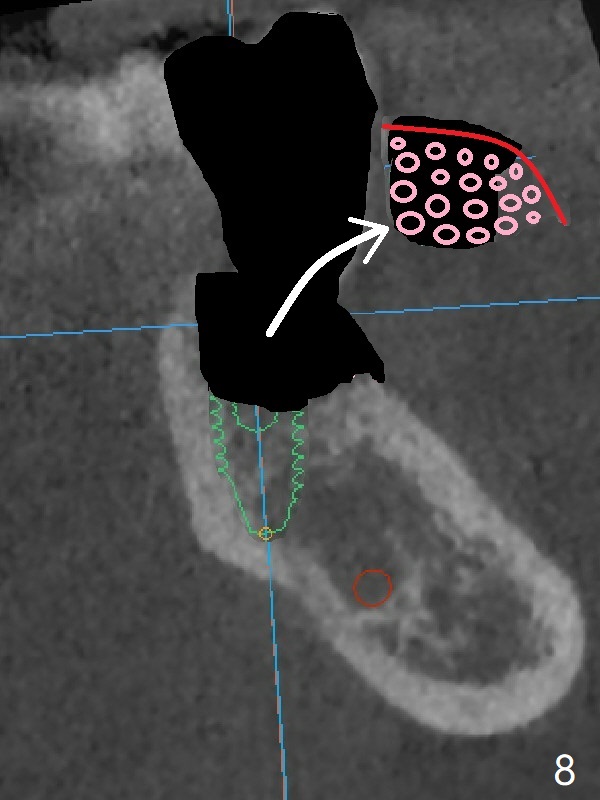

In contrast without implantation after extraction (Fig.6 (ignore green)), the socket may be grafted (Fig.7 pink circles) and covered by PRF membrane (red line). Due to the large socket with severe buccal defect, the graft is more likely to be lost (Fig.8). Several months later, an implant to be placed (Fig.9 green) will be short with unfavorable crown/implant ratio.